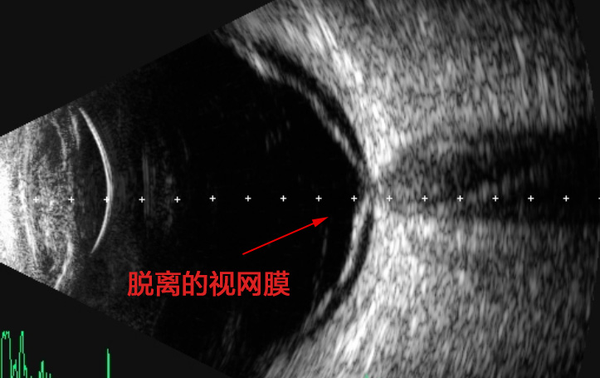

经检查,李先生是由于左眼视网膜上方12点半位置有一小裂孔,导致玻璃体腔的液体通过裂孔进入视网膜下间隙,使视网膜神经上皮层与色素上皮层分离,产生视网膜脱离。

“视网膜脱离就像一个相机的底片剥落了一样,如果不及时处理,感光细胞会因缺血缺氧而逐渐凋亡,造成永久性的视力损伤。”眼底病专家、爱尔眼科鄂豫区副总院长李玉军主任医师介绍。